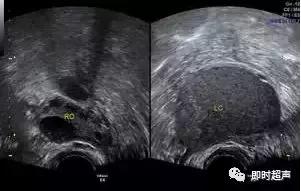

卵巢成熟囊性畸胎瘤(mature teratoma):常见,声像图表现多种多样。

卵巢畸胎瘤声像图,因其构成成分及比例不同而表现不一,可表现为“脂液分层征”、“面团征”、“瀑布征”、“雪花征”、“线条征”、“壁上结节征”、“杂乱结构征”7种特异性声像图。

具有典型声像图的畸胎瘤较易诊断,造成误诊或漏诊者主要发生在单一组织构成的畸胎瘤,这类畸胎瘤发生率低,且超声表现与常见的由多种组织结构构成的畸胎瘤超声特点不同。因此需与卵巢子宫内膜异位囊肿、浆液性囊腺瘤、单纯性囊肿等相鉴别。